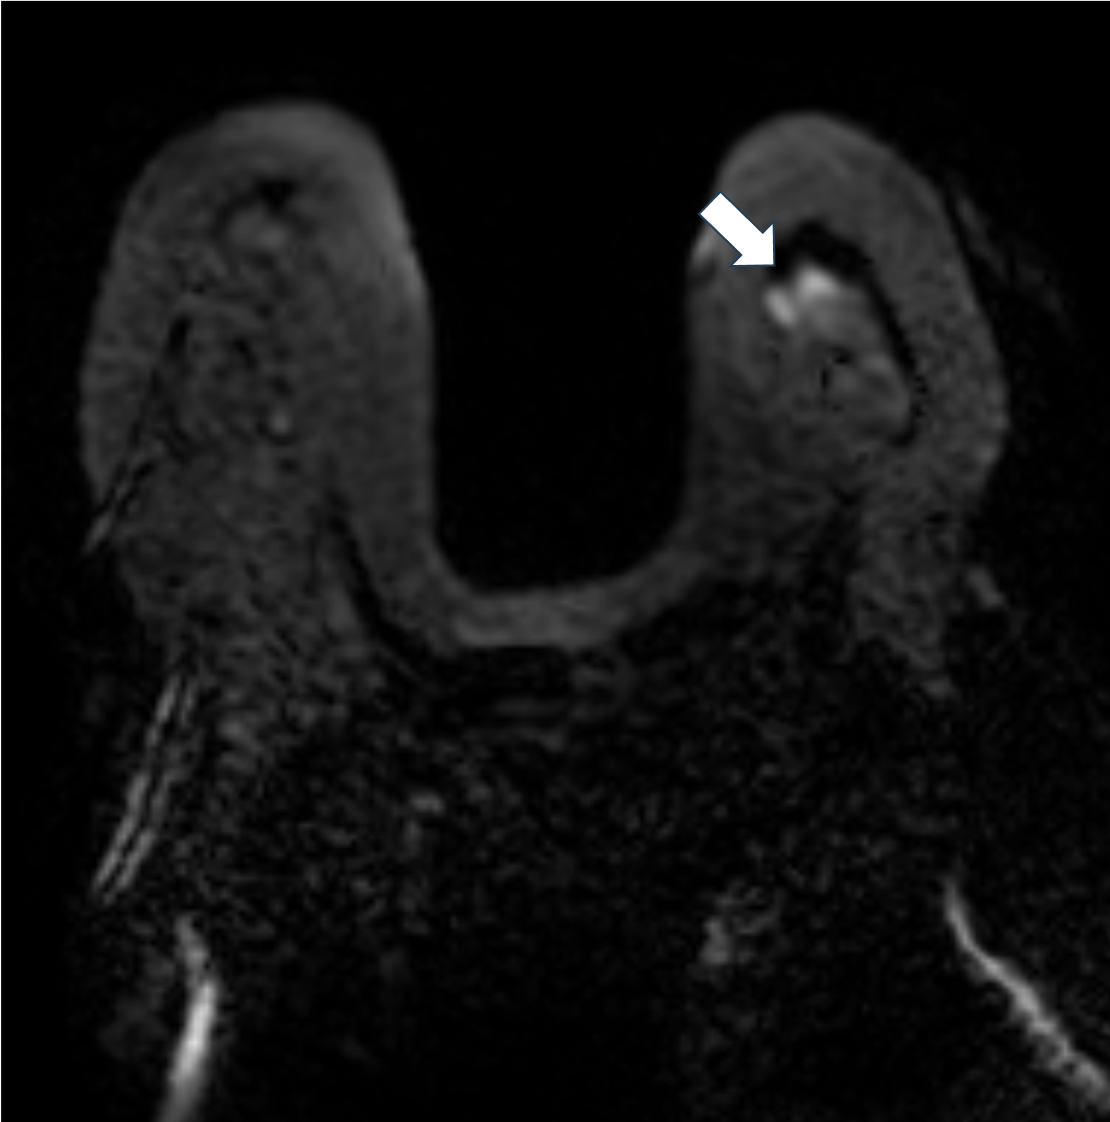

2. 脂肪抑制T2強調画像(造影前)

脂肪抑制T2強調像では腫瘤の乳頭側は軽度高信号を示すが、それ以外の部分は明瞭な高信号を示す。